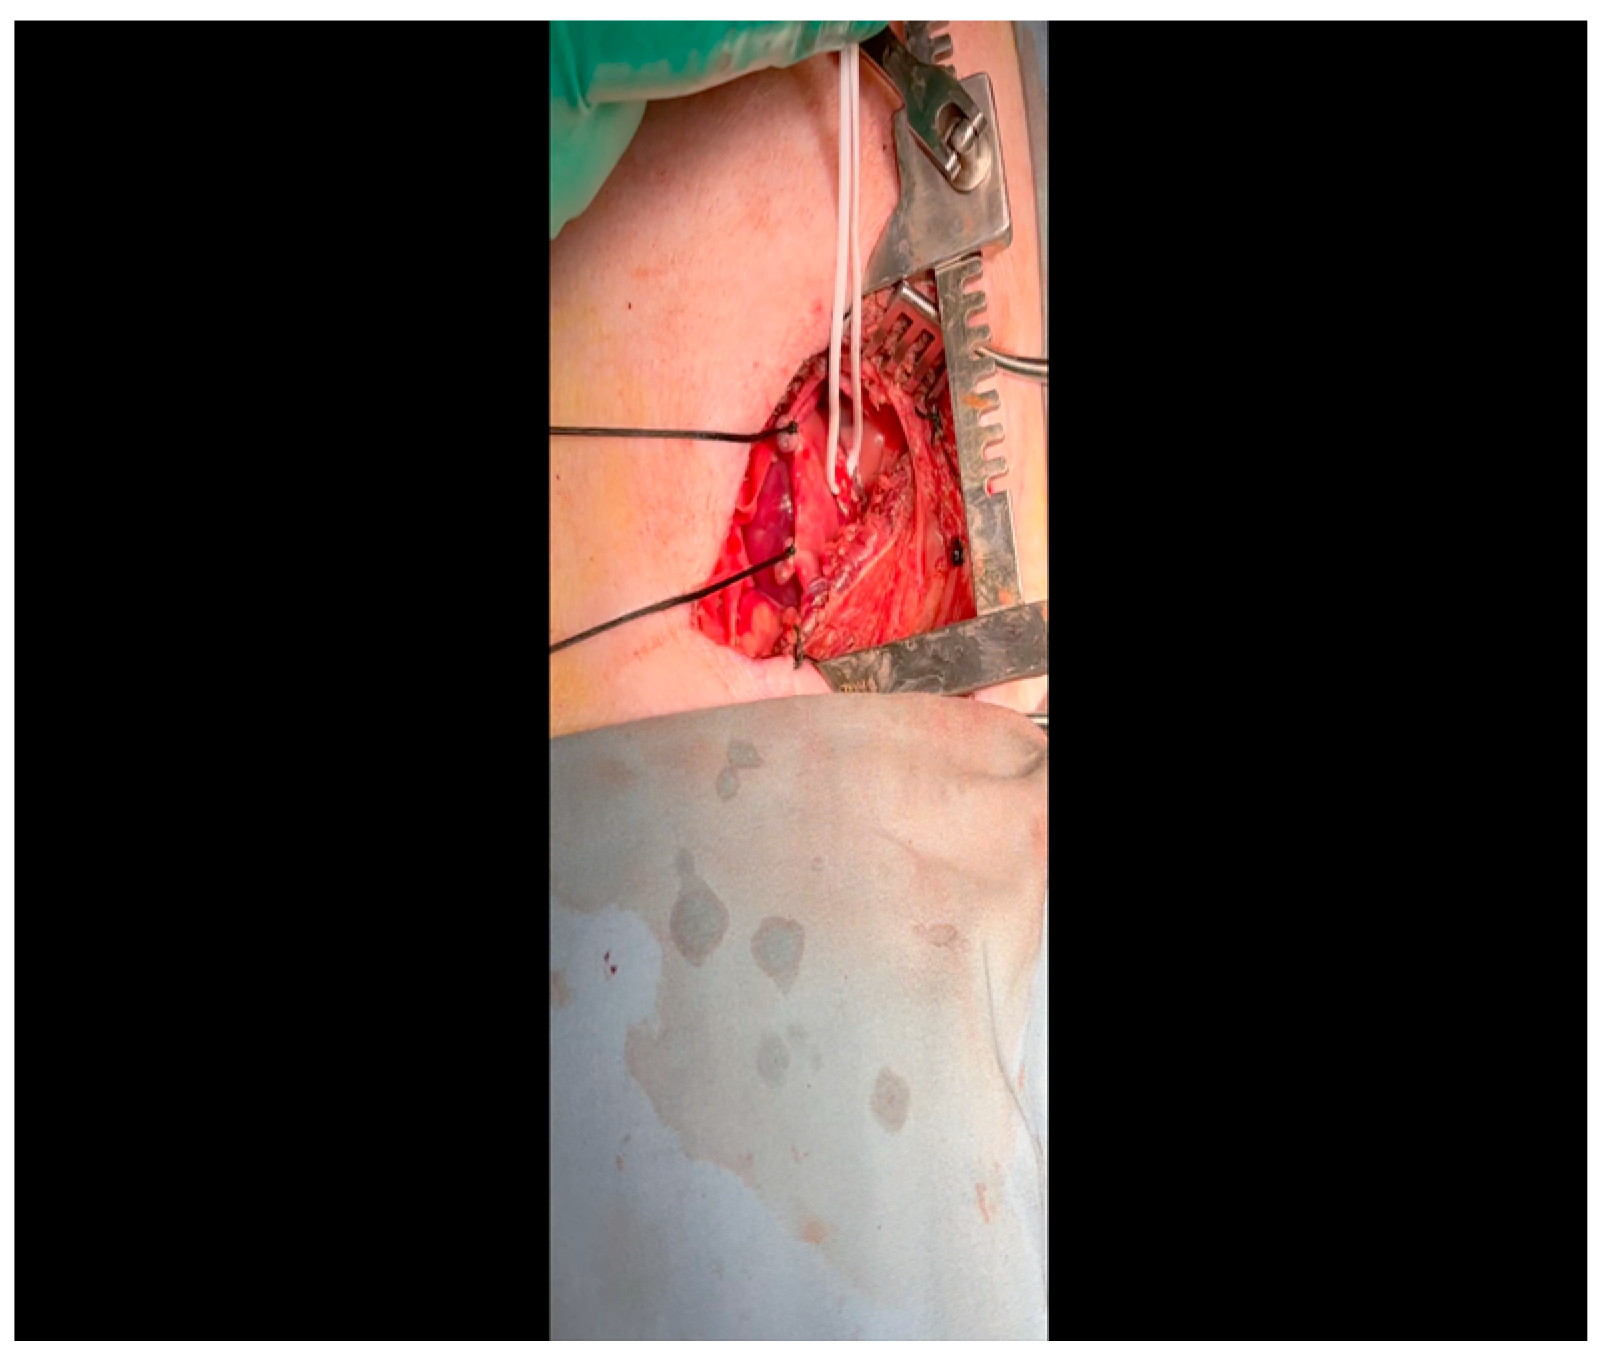

- A 3-0 silk suture secures the pericardium to the skin, elevating the heart into the surgical field and retracting the pericardium (Figure 4).